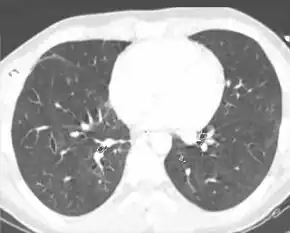

Computed tomography (CT scanning) is a more sensitive test for pulmonary contusion,[3][32] and it can identify abdominal, chest, or other injuries that accompany the contusion.[37] In one study, chest X-ray detected pulmonary contusions in 16.3% of people with serious blunt trauma, while CT detected them in 31.2% of the same people.[45] Unlike X-ray, CT scanning can detect the contusion almost immediately after the injury.[42] However, in both X-ray and CT a contusion may become more visible over the first 24–48 hours after trauma as bleeding and edema into lung tissues progress.[46] CT scanning also helps determine the size of a contusion, which is useful in determining whether a patient needs mechanical ventilation; a larger volume of contused lung on CT scan is associated with an increased likelihood that ventilation will be needed.[42] CT scans also help differentiate between contusion and pulmonary hematoma, which may be difficult to tell apart otherwise.[47] However, pulmonary contusions that are visible on CT but not chest X-ray are usually not severe enough to affect outcome or treatment.[36]